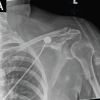

Radiographs of the knee revealed distal thigh subcutaneous and intramuscular emphysema (Fig. 3). MRI of the knee revealed a knee effusion, distal thigh fluid collections, and significant gas foci (Fig. 4). CT of the thigh also exhibited large multiseptated fluid collections in the anterior compartment of the thigh, gas to the level of the greater trochanter along fascial planes, a knee effusion, and diffuse soft-tissue edema (Fig. 5). LRINEC score was 9 [11-13]. The patient also complained of new-onset discomfort in the left shoulder and right posterior chest. A chest CT-scan revealed a gas-forming intramuscular abscess in his left infraspinatus muscle and a right posterior chest wall abscess without gas (Fig. 6).